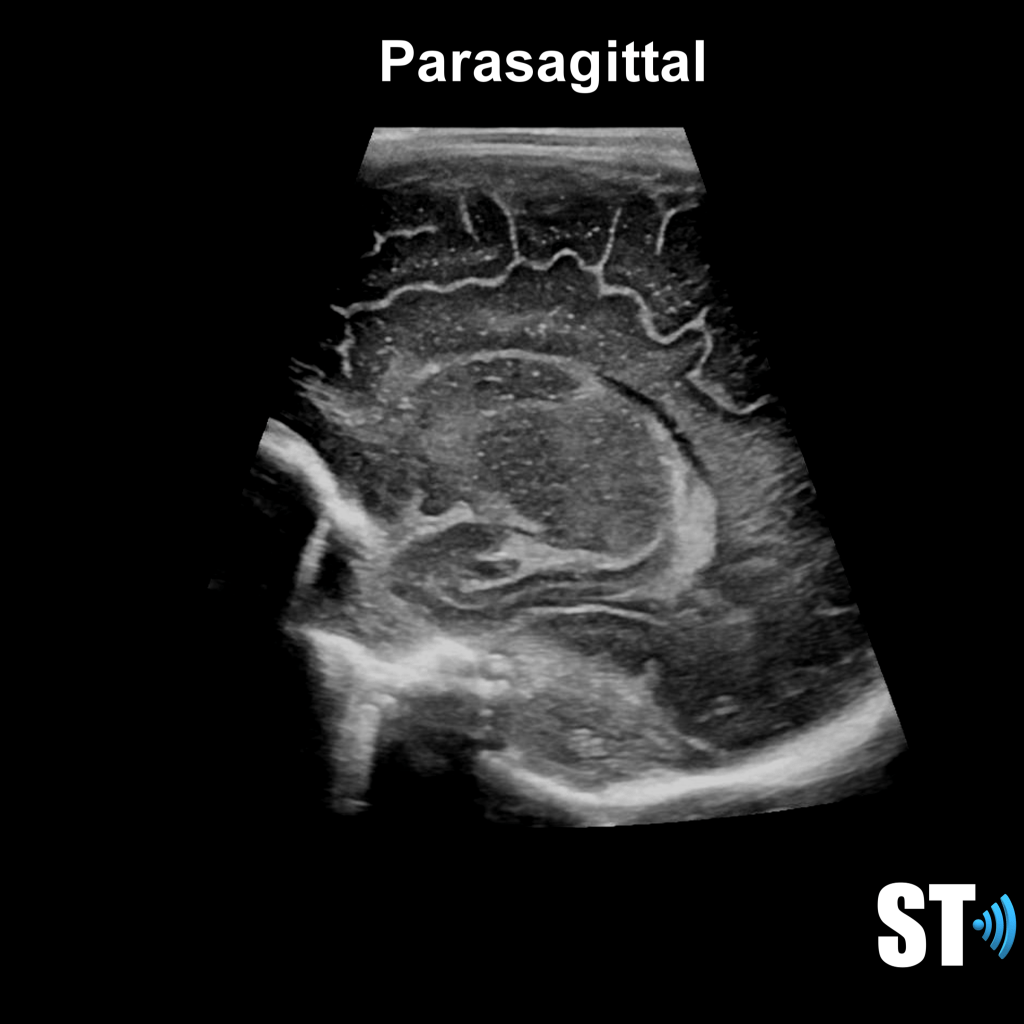

We use primarily the anterior fontanelle using a coronal, sagittal and parasagittal views. Also we scan through the mastoid fontanelle (for the posterior fossa and cerebellar views) and posterior fontanelle (for posterior structures especially the occipital horn to detect dependent hemorrhage) and temporal views for further evaluation.